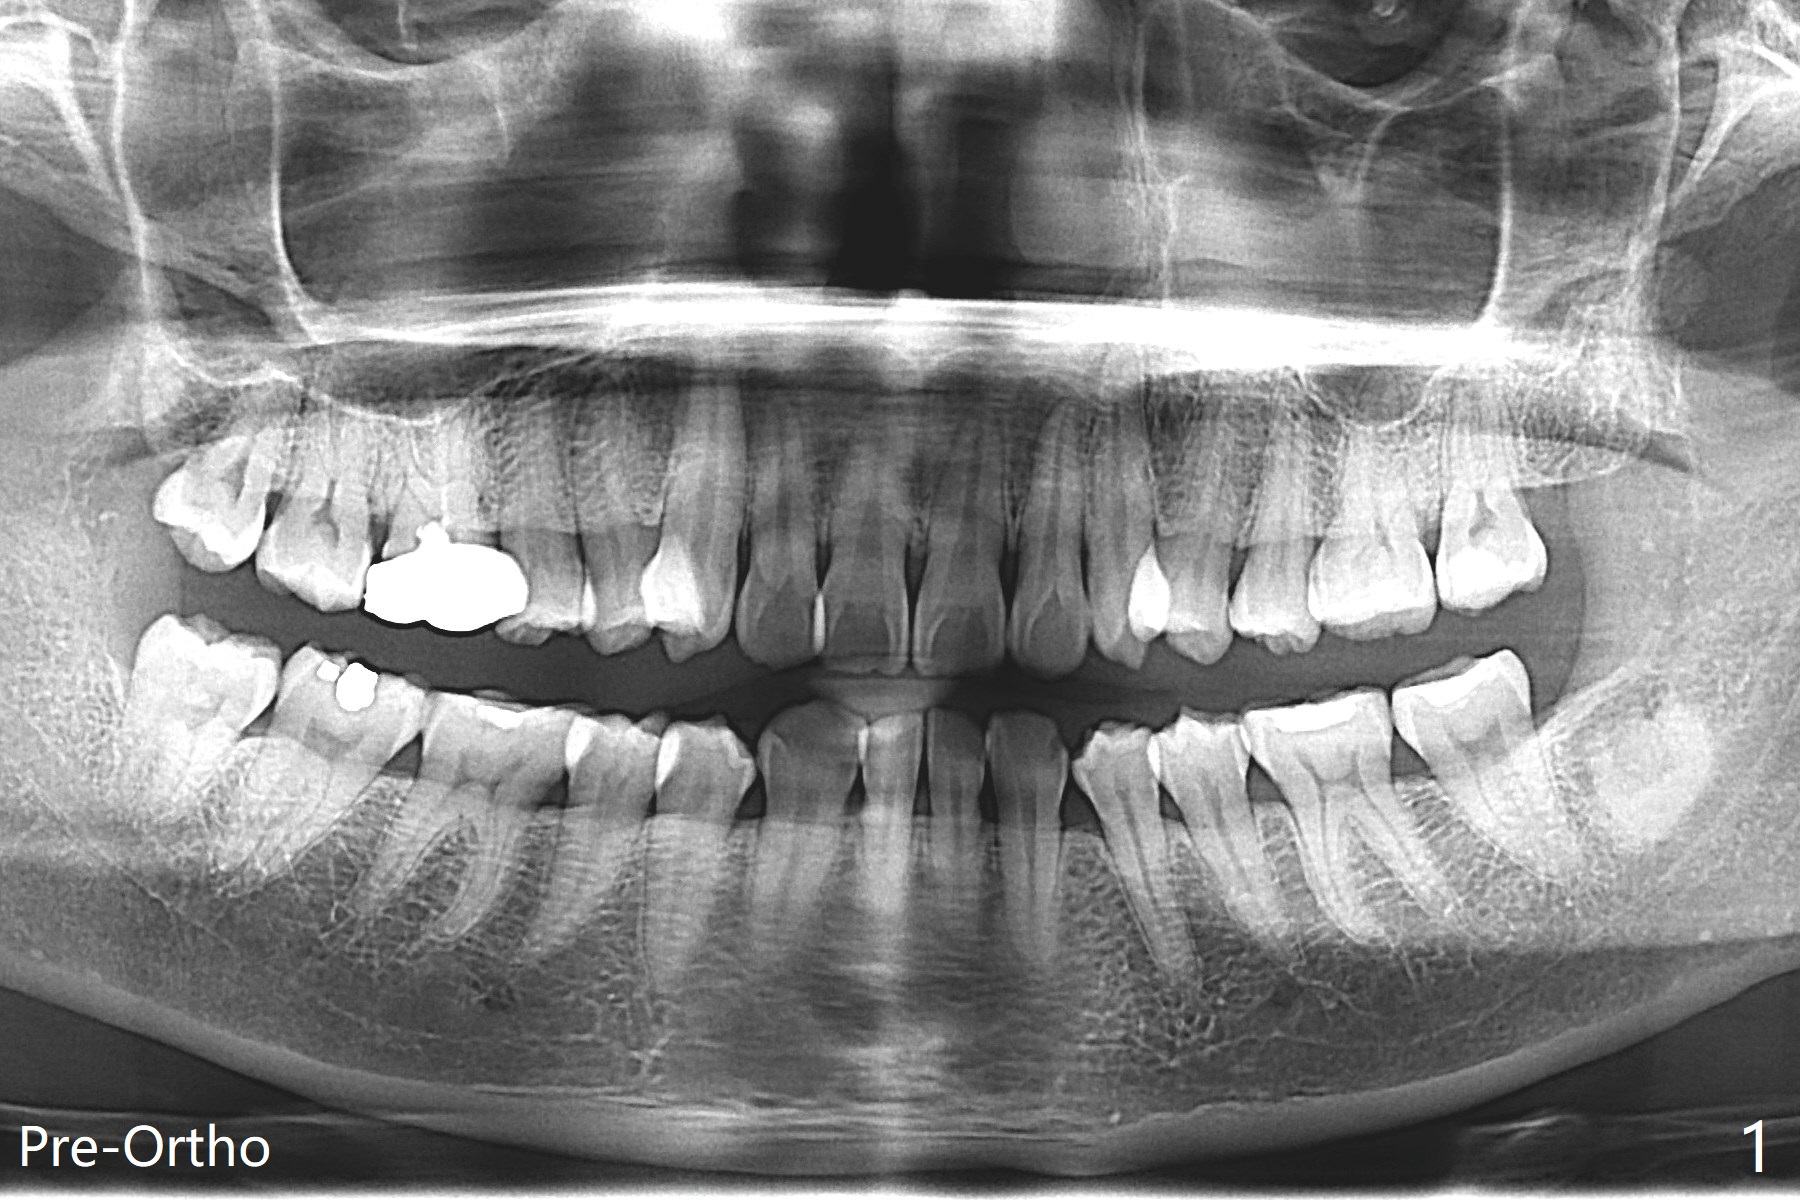

A 41-year-old woman with crowding (Fig.1) undergoes 2.5 year orthodontic treatment with extraction, leading to root resorption of the maxillary anterior teeth (Fig.2-4).